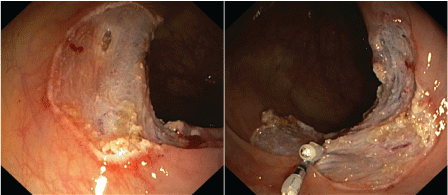

A 68-year-old man live with a prosthetic aortic valve and treated with a vitamin K antagonist was admitted to our department for control colonoscopy 10 years after sigmoid resection due to previous adenocarcinoma. Before the procedure, coumarin was replaced by low-molecular weight heparin. After complete colonic preparation the colon was viewed up to the ileocoecal junction. During colonoscopy a 3 cm long polyp was resected by Endoscopic Mucosa Resection (EMR) in the ascending colon (Figure 1). On the base of this area, a deeper mucosal hiatus was clipped. Furthermore, an approximately 6 cm long sessile polypus was detected in the sigmoid colon, which was extracted in pieces. No complications were detected through the examination. Two hours after colonoscopy the patient complained of a swollen neck, with pain in his neck, as well as mild shortness of breath without any abdominal pain. On physical examination crepitus was palpated in the neck and upper thorax of the patient, clearly signs of subcutaneous emphysema. Breathing sounds were normal. On physical examination the abdomen was palpable, soft, tenderness was not detected and normal bowel sounds were heard. The patient was hemodynamically stable, conscious, and afebrile. Chest and abdominal x-rays showed 26 mm wide left subdiaphragmatic air. Air was also detected in the mediastinum continuing to the aorta, as well as cervical subcutaneous emphysema (Figure 2). Initial laboratory parameters were in the normal range, C-reactive protein was 3.4 mg/l, and white blood cell count was 7020/μl. As perforation was suspected, 400 mg b.i.d. ciprofloxacin and 500 mg t.i.d. metronidazole combined intravenous antibiotic therapy was started immediately. The patient was transferred to the surgical department for further observation. Because symptoms of peritonitis were not present and inflammatory laboratory tests remained in a normal range, conservative therapy i.e. combined broad spectrum antibiotics and a fasting regimen was continued. On control x-rays, the amount of air decreased everywhere. On the 3rd hospital day, hematochezia causing anaemia was detected. Control colonoscopy detected no active bleeding signs and no signs of perforation. In the ascending colon, clear base of mucosectomy with clips were seen. A 3 cm large remnant polyp was seen in the sigmoid colon, the base of the previous sigmoid polypectomy was fixed and could not be resected with colonoscopy. After transfusion the patient was stable. Histology of the sigmoid tumor revealed adenoma with high grade dysplasia with focal carcinoma that was limited to the mucosal layer. Because of this finding, the patient went through open sigmoid resection one month later. During surgery a retroperitoneal inflammatory mass was detected next to the sigmoid colon. The excised specimen was histologically diagnosed as villous adenoma with high grade dysplasia. No residual tissue was identified at the resection margins. He was discharged fully recovered. Oncological follow-up of the patient will be continued.

Figure 1: In ascending colon a 3 cm long flat polyp was resected by endoscopic mucosa resection with piecemeal technique. A deeper mucosal hiatus was closed with two haemoclips. View Figure 1